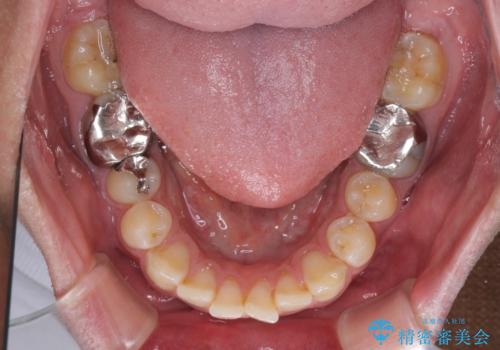

- 矯正装置

- メタルブラケット

- 前歯のデコボコを気にして来院された患者様です。

ワイヤー装置でもマウスピースでも対応可能でしたが、自己管理の煩わしさを気にされ、ワイヤー装置にて矯正治療を行うこととしました。

矯正治療後は、奥歯の銀歯をセラミッククラウンにて補綴治療を行うこととしました。